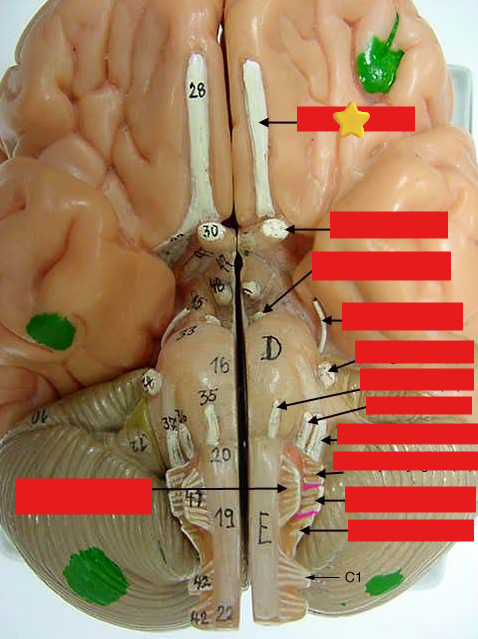

cranial nerves

12 Terms

1

olfactory

2

optic

3

oculomotor

4

trochlear

5

trigeminal

6

abucens

7

facial

8

vestibulocochlear

9

glossopharyngeal

10

vagus

11

accessory

12

hypoglossal